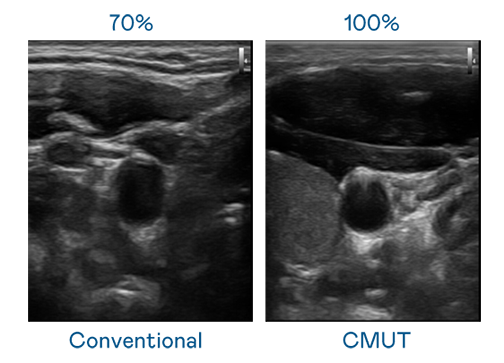

CMUT 技术是一种用电容式微机电元件来产生超音波讯号的技术。与传统 PZT 压电式技术相比,CMUT 频宽增加 30%,更宽频的超音波讯号让影像解析度大幅提升,是实现高影像品质医疗超音波扫描、促进精准医疗发展的关键技术。

大频宽带来超清晰影像

超音波影像的解析度高低,首先取决于探头能发出的讯号频宽。星际娱乐 CMUT 可提供高清晰的超音波讯号,提供高频宽、高灵敏度、影像纹理细节更高的超音波影像,协助医护人员缩短影像判读时间及利用精准的医疗影像进行诊断。